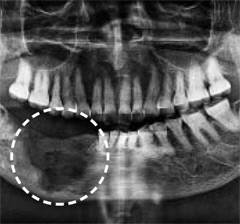

골다공증 치료제를 투여하고 있으면 치아를 뽑은 뒤 회복이 늦어져 턱뼈가 괴사할 위험이 커진다. 이런 위험을 막기 위해선 발치 전 골다공증 치료제를 충분한 기간 동안 중단하는 것이 좋다는 연구 결과가 나왔다.

정상적인 뼈는 낡거나 손상된 조직을 제거하는 ‘골흡수’와 새로운 뼈를 만드는 ‘골형성’이 균형을 이뤄 유지된다. 하지만 골다공증 환자의 뼈는 골흡수 속도가 빨라져 점차 가늘고 약해진다. 치료를 위해선 골흡수를 억제해 골밀도를 유지·상승시키는 치료제인 ‘졸레드로네이트’나 ‘이반드로네이트’를 환자 상태에 맞춰 투여한다. 다만 약의 효과로 골흡수가 지나치게 억제되면 낡은 뼈가 잘 제거되지 않고 손상이 누적될 수 있는데, 특히 턱뼈는 이런 상태에서 발치나 임플란트 등 치료를 시행하면 회복이 지연돼 괴사로 이어지기 쉽다.

연구진은 발치 전 효과적인 골다공증 치료제 중단 시점을 분석했다. 그 결과 중단 기간이 길수록 턱뼈 괴사 발생 위험이 유의미하게 감소하는 것으로 나타났다. 턱뼈 괴사 발생률은 약물을 90일 이하 중단한 그룹(1.28%)에서 91~180일 중단한 그룹(0.71%), 365일 이상 중단한 그룹(0.42%)으로 갈수록 낮아졌다.

약물 종류에 따라서도 중단 기간이 턱뼈 괴사 발생률에 미치는 영향에서 차이를 보였다. 이반드로네이트는 91일 이상만 중단해도 괴사 발생률이 크게 감소한 반면, 졸레드로네이트는 1년 이상 중단해야 괴사 발생률이 효과적으로 줄었다. 연구진은 졸레드로네이트의 반감기가 더 길어 체내에 오래 남아 작용하기 때문이라고 설명했다.